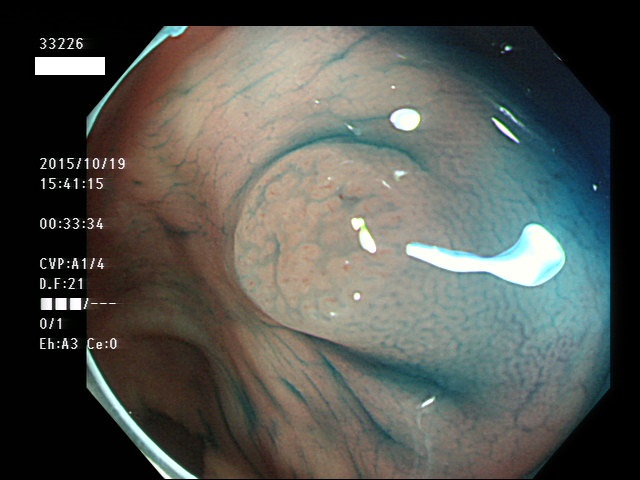

上記100名より抽出した平坦・陥凹型腺腫(=癌化の危険が高いが見落としやすい病変)の内視鏡写真